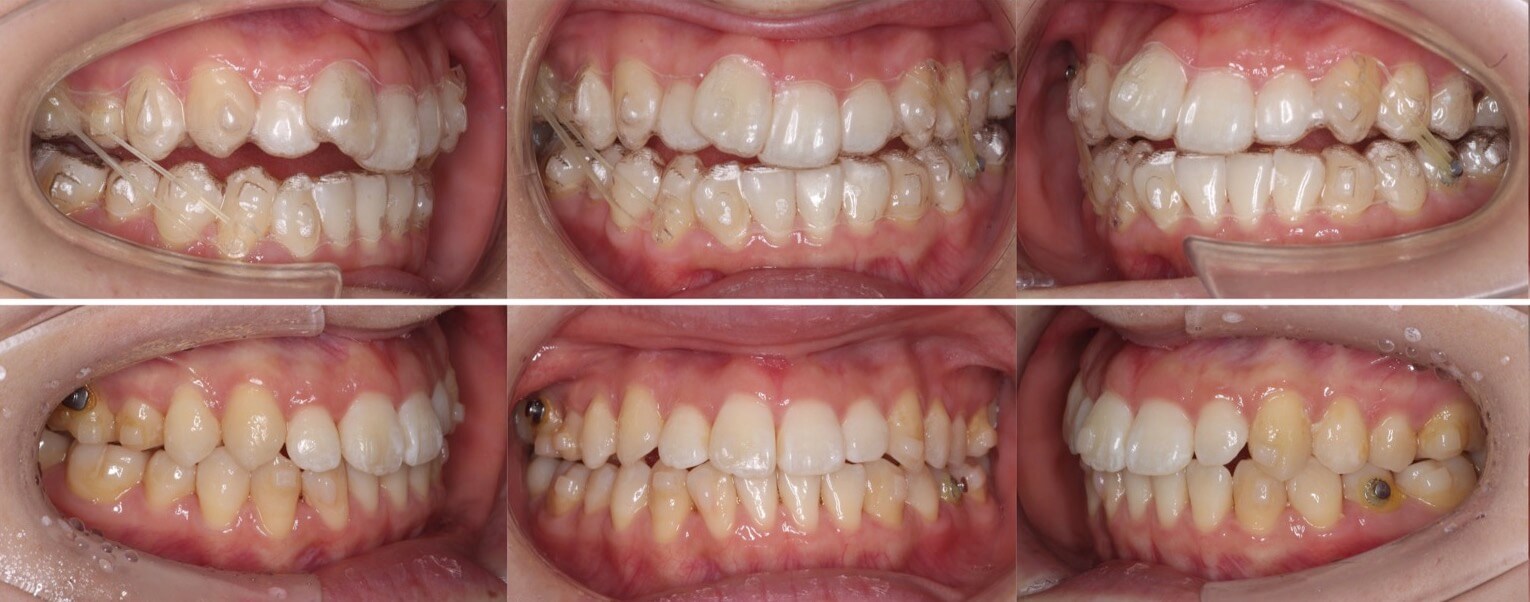

高校生女性・中程度叢生・唇側矯正装置・抜歯

八重歯と上下の正中線の不一致があるケースです。左右の抜歯部位を変えたり、下の歯並びをIPRも併用して顎間ゴムで回転させることで正中線を上下の正中線を一致させました。骨格に大きな非対称がなかったため上手くいったケースになります。

<症例概要> 難易度★★★☆☆

主訴:でこぼこ

年齢・性別:高校生女子

住まい:千葉県八千代市

症状:叢生・正中線不一致

治療方針:抜歯空隙閉鎖・右下後方移動・IPR

抜歯:右上第二小臼歯・左上第一小臼歯

治療装置:唇側矯正装置

治療期間:1年11か月

リテーナー:上下プレートタイプ+フィックスタイプ

治療費用:968,000(税込)

代表的副作用:痛み・治療後の後戻り・歯根吸収・歯髄壊死・歯肉退縮

高校生女性・中程度叢生・マウスピース型装置

左側の片側のみに八重歯があり、上下の正中線が不一致となっている症例です。前歯のかみ合わせも上下がしっかりと当たるようになり健康な歯並びになりました。

主訴:八重歯

年齢・性別:高校生女性

住まい:千葉八千代市

症状:叢生・正中線の不一致

治療方針:上顎後方移動・IPR

治療装置:マウスピース型矯正装置(アライナー装置)

治療期間:1年7か月

アライナー枚数:49+16+15ステージ

リテーナー:上下+クリアタイプ

治療費用:990,000(税込)

▶︎その他の副作用

顎間ゴムを使用して、左上にスペースを作り八重歯を下ろしてきました。